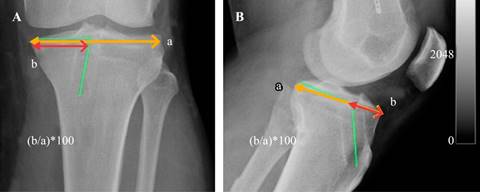

Para evaluar la ubicación del túnel tibial6 se midió la ubicación en porcentaje de la localización con respecto al platillo tibial en el frente, se midió el ancho del platillo tibial y la distancia entre el extremo medial del platillo y el centro del túnel tibial expresado en forma porcentual. En el perfil se midió la distancia anteroposterior del platillo tibial interno y la distancia de la cara anterior de la tibia al centro del túnel tibial expresado en forma porcentual. El ángulo del túnel tibial en el frente es evaluado por una línea que pasa por el platillo tibial interno y su intersección con una línea que pasa por el centro del túnel tibial. El ángulo de inclinación del túnel tibial en el perfil es medido por una línea que pasa por el platillo tibial interno de anteroposterior y otra línea que pasa por el centro del túnel tibial que lo intercepta (Figura 2).

Figura 2: A) Distancia mediolateral del platillo tibial (a ) y la distancia del túnel tibial a la cortical medial (b ) y la medición porcentual. La línea verde evidencia el ángulo del túnel tibial. B) Distancia posteroanterior del platillo tibial interno (a ) y la distancia del túnel tibial a la cortical anterior (b ). El ángulo del túnel tibial con respecto al platillo tibial (línea verde).